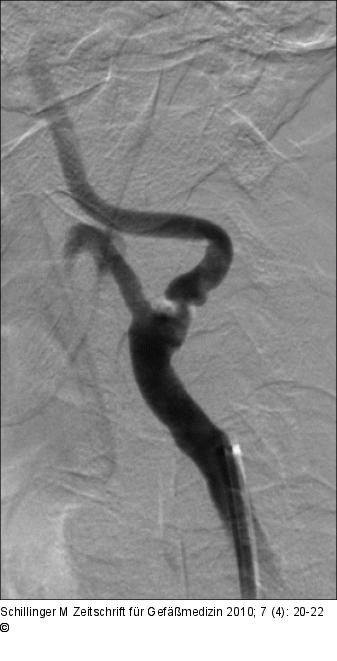

Abbildung 4: Karotisstenose Fall 2: Angiographie der hochgradigen, asymptomatischen Karotisstenose. |

Fall 2: Angiographie der hochgradigen, asymptomatischen Karotisstenose. |